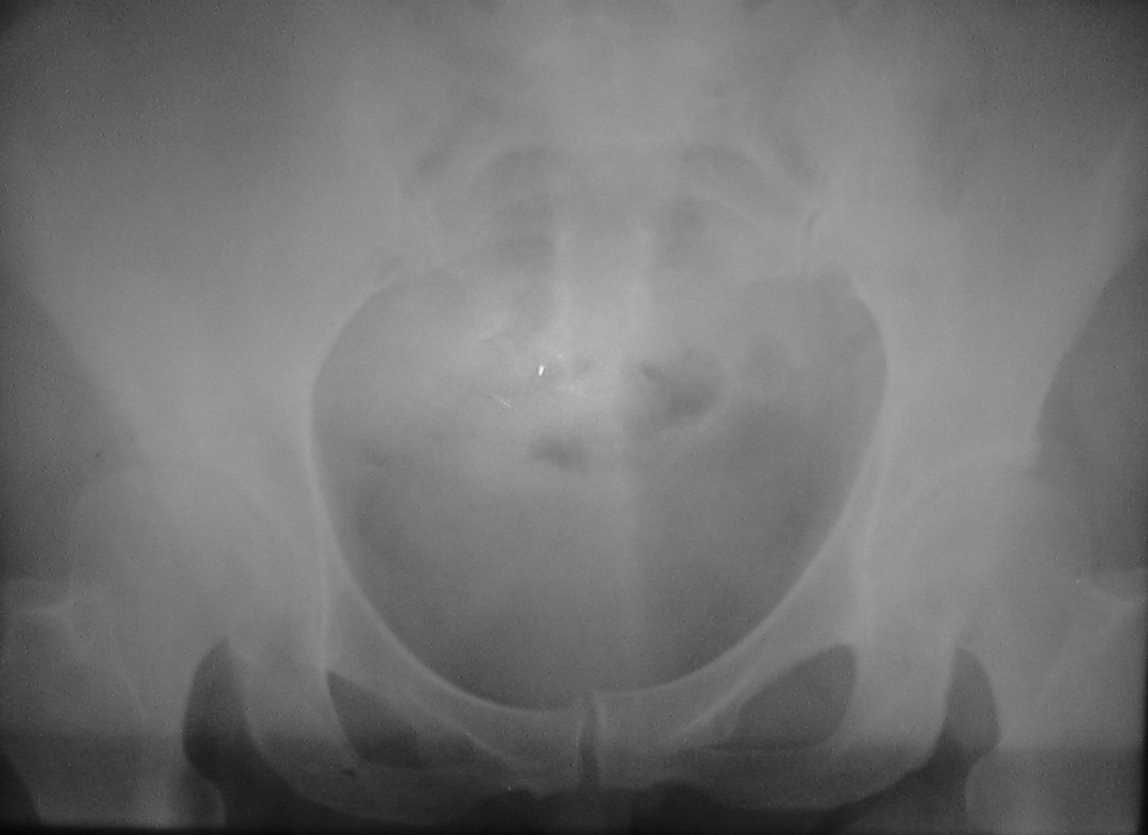

Спасибо всем,кто откликнулся, высылаю

обзорные снимки таза. Прошу извинения за качество снимков

Ну что уж извиняться, лучше повторить Ртг :-), да и клинику уточнить с акцентом на предыдущ. вопросы. Если нет признаков воспаления - почему не стрессовая киста?